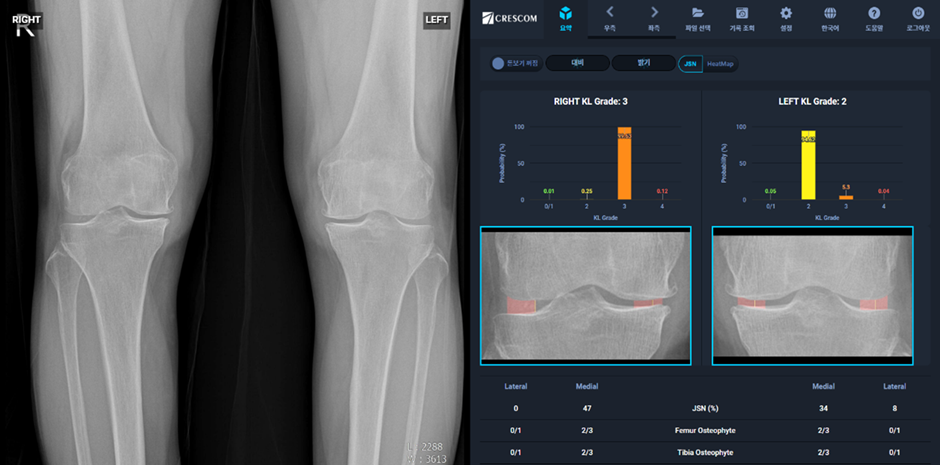

근골격계 의료데이터 인공지능 분석 솔루션에 특화된 주식회사 크레스콤(대표 이재준)은 지난 5일 KL 등급 기반의 무릎 관절염 심각도 정량화 자동분석 인공지능 소프트웨어 ‘MediAI-OA(메디에이아이-오에이)’의 2등급 의료기기 제조 허가를 취득하였다고 밝혔다. (제허 24-247호)

‘MediAI-OA’는 전 세계적으로 사용하는 무릎 관절염의 심각도 기준인 “KL 등급”과 골극(Osteophytes, 뼈의 끝부분에 새롭게 자라난 뼈) 형성 여부, 무릎 관절간격의 정상군 대비 감소 정도를 정량적으로 제공하는 국내 최초의 인공지능 솔루션이다.

크레스콤은 이러한 임상현장의 편차 해소 요구와, 건강보험심사평가원 및 과학기술정보통신부의 정량적 평가 솔루션 개발 요청에 따라, 특허 기반의 ‘무릎 관절 간격 감소(Joint Space Narrowing; JSN) 비율’을 자동으로 정량화하여 정상기준 대비 감소율을 백분율로 표시하는 인공지능 기술을 적용하고, 여러 주요 질환 지표를 통합 반영한 인공지능 무릎 관절염 심각도 기준인 KL 등급을 확률로 제공한다.

식약처의 허가 확증 임상시험 결과에서 4명의 의사가 단독으로 KL등급 판정 시에 정답인 참조표준과의 kappa값 평균이 0.57 로 정답과의 일치도가 낮았으나, 4명의 의사가 MediAI-OA를 참고하여 KL등급을 판정했을시 참조표준과의 kappa값 평균이 0.88로 정답과의 일치도가 현저히 향상함을 확인하였다.